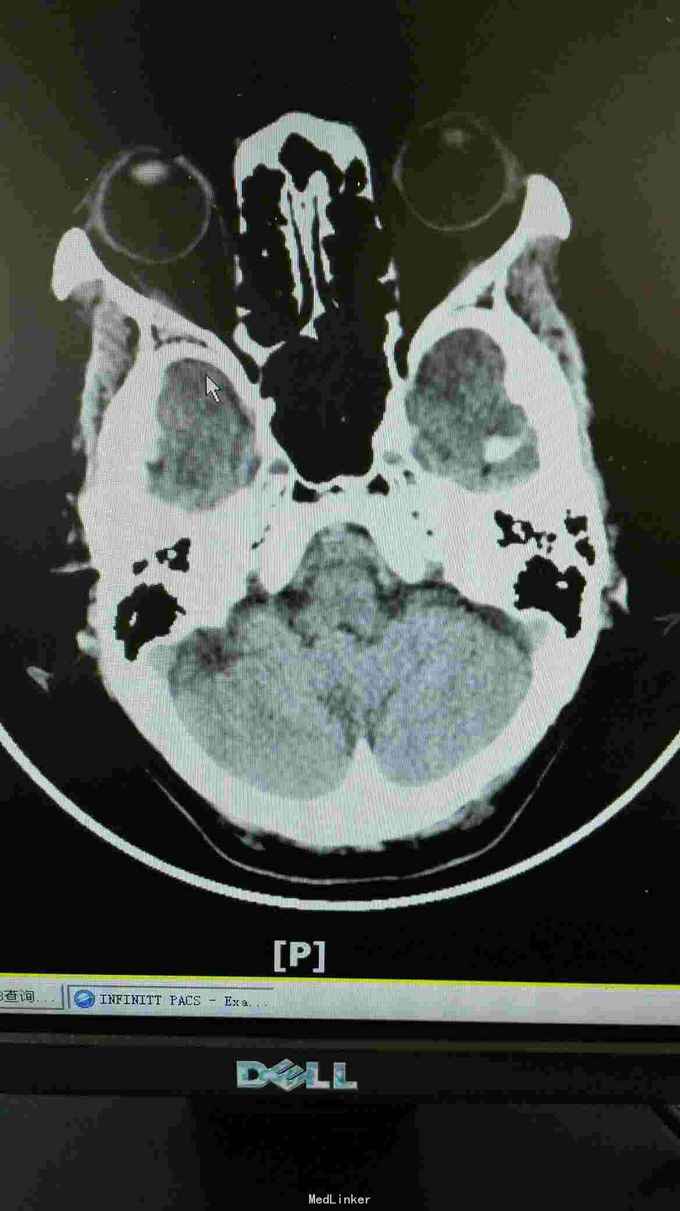

生命体征:耳温:36.8℃ 脉搏:96次/分 呼吸:20次/分 血压:140/67mmHg。pain score: 0/10 发育无异常,口唇无发绀,双肺呼吸音清,未闻及干湿性啰音;心率96次/分,律齐,未闻及明显病理性杂音;腹软,无压痛、反跳痛,肝脾肋下未及,双肾区无叩痛,双下肢无浮肿。神经专科:神清,构音尚清,双侧额纹对称,双眼睑下垂,右侧明显,双侧瞳孔等大等圆,直径约3.0mm,对光++,双眼活动尚可,伸舌居中,鼻唇沟无浅,颈软,四肢肌力5级,双侧肢体肌张力对称,双侧巴氏征未引出,双侧指鼻准,闭目难立征阴性。 血常规三系尚正常。出凝血系列,甲状腺功能 ;存在TSH偏高。肿瘤标志物基本正常范围。糖化血红蛋白正常范围;空腹血糖、血钾正常范围。大小便常规未见明显异常。 胸部CT提示右肺中叶及左肺上叶舌段纤维、增殖灶,请结合临床。颈动脉B超提示左侧颈动脉斑块形成,存在左侧颈动脉硬化。椎动脉B超提示双侧椎动脉未见明显异常。心超提示左室舒张功能下降。腹部B超提示肝、胆、胰、脾未见异常,双肾、输尿管、膀胱未见异常。甲状腺B超提示右侧甲状腺结节。肌电图提示重频试验阴性。心电图提示窦性心律,大致正常心电图。 这个病人因为做过钢板内固定术,所以磁共振没做!可惜了

诊断:双眼睑下垂待查:重症肌无力?动眼神经麻痹待排。2.高血压病?3.心功能不全? 目前治疗上予立普妥20mg调脂稳定斑块,待肌电图检查回报后余新斯的明口服,以及活血化瘀、改善循环等对症支持治疗.

这患者优先考虑重症肌无力,但是以单侧为主,所以动眼神经麻痹也需要排除,因为患者在上级医院做过“新斯的明试验”症状稍改善,持续数小时后又加重,所以等药效过了之后给她做了肌电图,重频试验阴性。1-5波幅下降不明显,结合头颅CT结果,诊断重症肌无力,予新斯的明口服后症状是有改善, 我想请教各位,单单从症状和新斯的明试验可以诊断重症肌无力吗?因为这个病人的肌电图表现是阴性的胸部CT也没看到有胸腺增生。